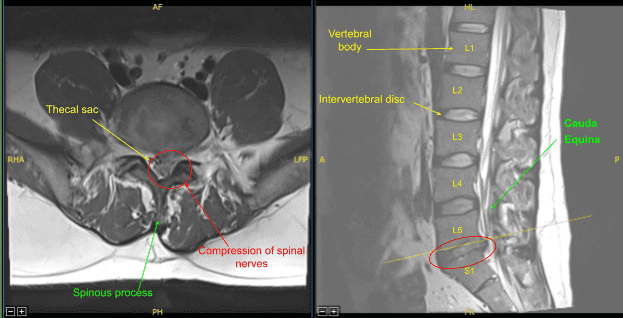

Se realizó resonancia magnética (RM), que mostró una hemilaminectomía previa izquierda en L5-S1. La hernia/extrusión del disco central izquierdo en L5-S1 contribuye al borrado del saco tecal y del receso lateral izquierdo, con estenosis y efecto de masa severa sobre las raíces nerviosas descendentes de S1 izquierda y al menos S2.